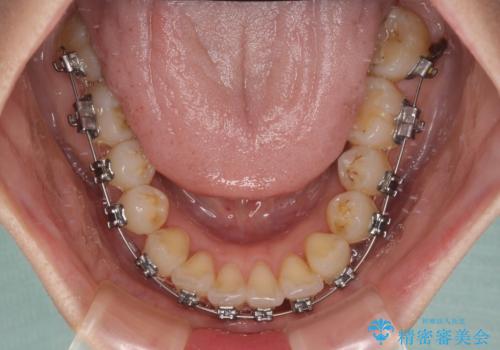

奥歯の噛み合わせをみると、上顎歯列が全体的に前突している状態であり、この咬み合わせのまま歯列を整えると出っ歯になってしまう可能性がありました。

アンカースクリューと補助装置を使用して上顎大臼歯を遠心移動させることで咬み合わせを改善し、ワイヤー装置によりデコボコを解消しながら口元の突出感も改善していくこととしました。